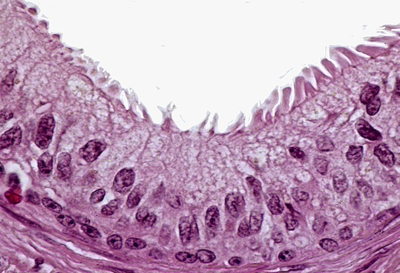

Cils = ils bougent de manière synchrone (dépendants les uns des autres) pour faire avancer les produits de sécrétion de manière efficace

Villosités = expansion de la membrane qui possède un cytosquelette avec des microtubules : chaque villosité bouge de manière indépendante

Stéréocils = c'est aussi une expansion de la membrane avec un squelette d'actine mais pas de microtubules ce qui les rend immobiles ! Ils sont plus sinueux que les villosités et s’emmêlent entre eux.